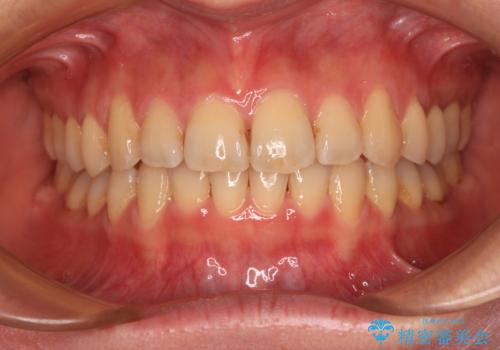

[ マウスピース矯正 ] 出っ歯に見える前歯を改善したい

![[ マウスピース矯正 ] 出っ歯に見える前歯を改善したいの症例 治療前](https://seimitsushinbi.jp/wp/wp-content/uploads/2023/10/IMG_6858-500x350.jpg?v=1697014973)

![[ マウスピース矯正 ] 出っ歯に見える前歯を改善したいの症例 治療後](https://seimitsushinbi.jp/wp/wp-content/uploads/2023/10/8a6c9bf89570c0c75da0a5fabd1cd70e-500x350.jpg?v=1697014858)